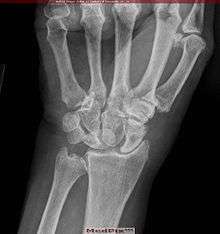

The instability of joints, leading to (sub)luxations and joint pain, often require surgical intervention in patients with Ehlers–Danlos syndrome. Instability of almost all joints can happen but appear most often in the lower and upper extremities, with the wrist, fingers, shoulder, knee, hip, and ankle being most common.[40]

Common surgical procedures are joint debridement, tendon replacements, capsulorraphy, and arthroplasty. Studies have shown that after surgery, degree of stabilization, pain reduction, and patient satisfaction can improve, but surgery does not guarantee an optimal result: Patients and surgeons report being dissatisfied with the results. Consensus is that conservative treatment is more effective than surgery,[20] particularly since patients have extra risks of surgical complications due to the disease. Three basic surgical problems arise due to EDS: the strength of the tissues is decreased, which makes the tissue less suitable for surgery; the fragility of the blood vessels can cause problems during surgery; and wound healing is often delayed or incomplete.[40] If considering surgical intervention, it would be prudent to seek care from a surgeon with extensive knowledge and experience in treating patients with EDS and joint hypermobility issues.